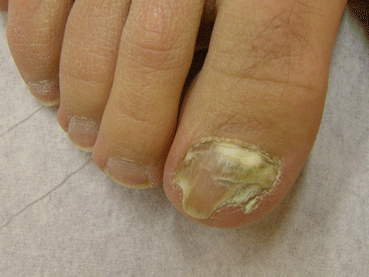

Fig. 4.9

SWO and DLSO affecting the same nail

Fig. 4.10

SWO emerging from proximal nail fold and DLSO